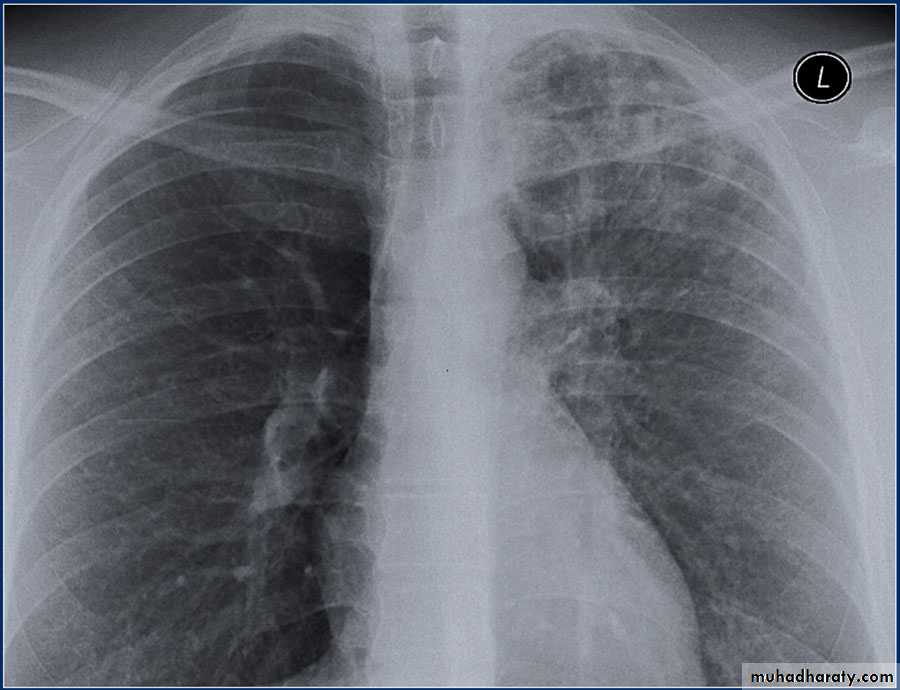

History: dyspnea, weight loss, dehydration with poor immunity